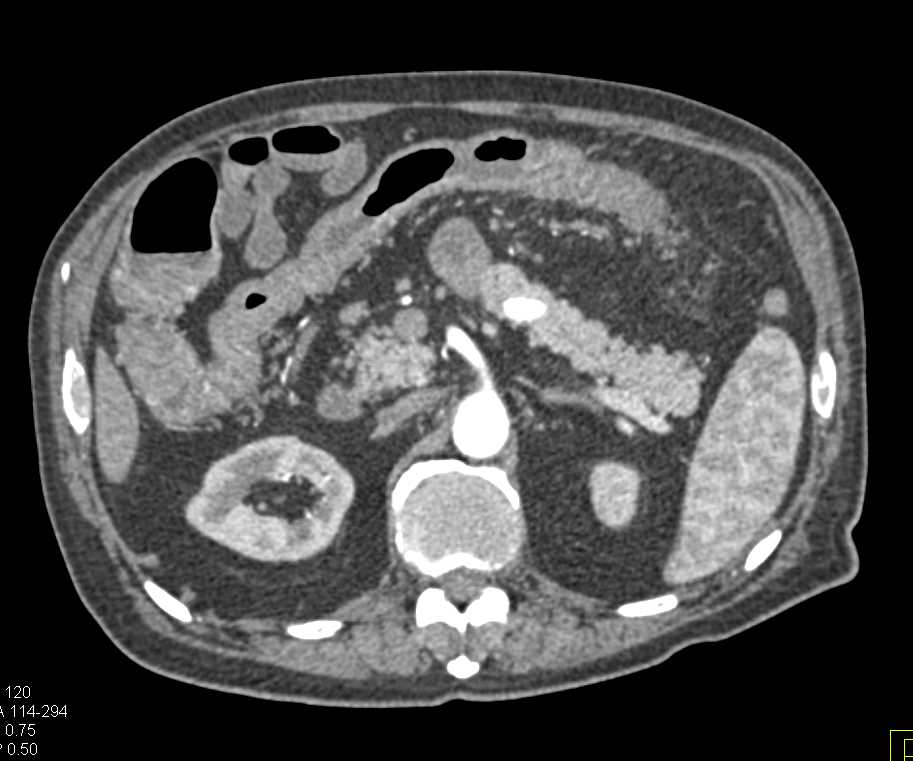

Crohn's Disease